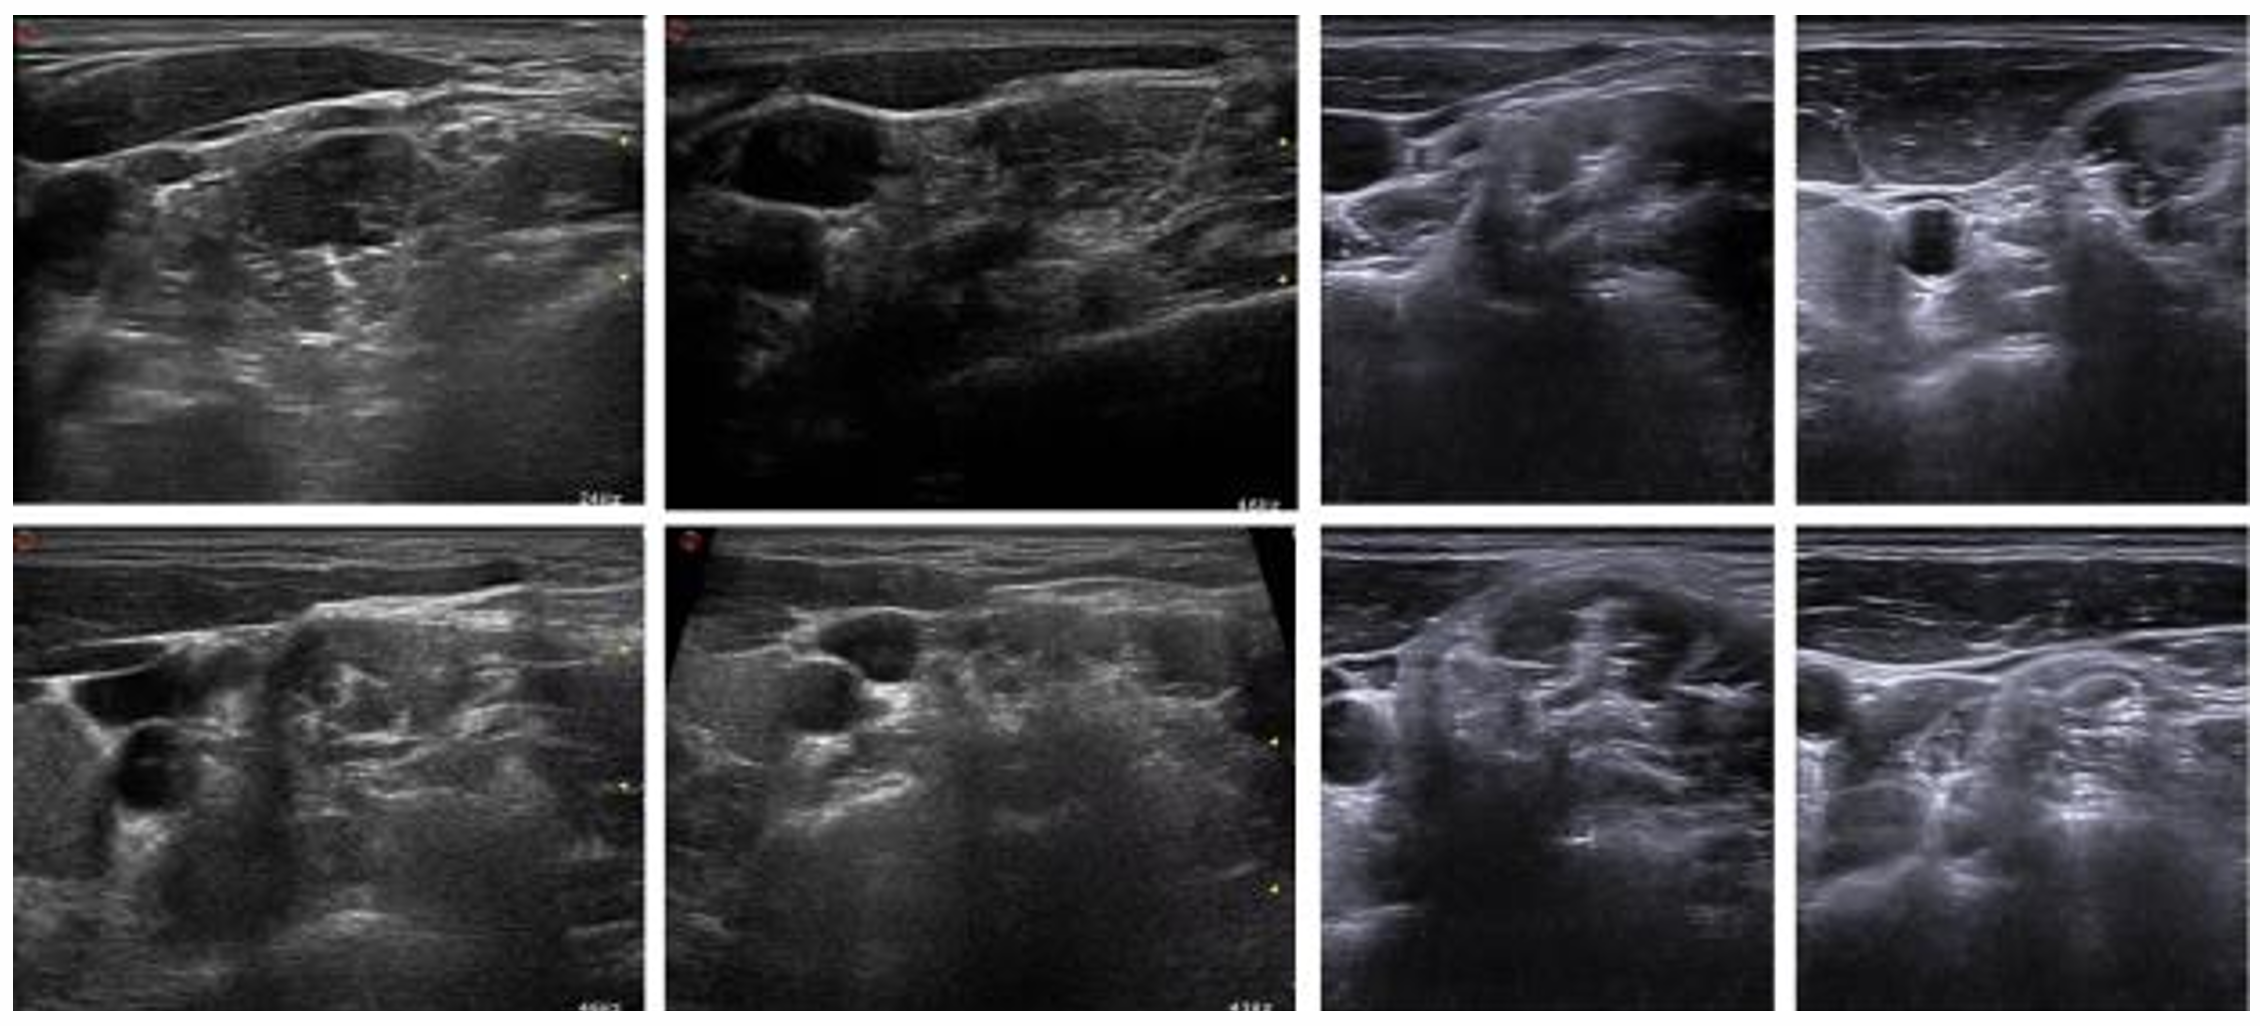

From the 101 recordings, 10–15 frames were randomly selected from each, resulting in a total of 1,052 images. Each image was annotated by an anesthesiologist using LabelMe software, identifying four anatomical structures: artery, vein, nerve, and muscle. The nerve is characterized by an approximate diameter of 3 mm, featuring a bright outer boundary and a darker interior region. Representative images and annotations are shown in Figure 1.

Refer to caption

Figure 1: Representative ultrasound images of the brachial plexus with expert annotations for artery, vein, nerve, and muscle.

While the original study mentions both ultrasound models, the publicly available dataset contains 955 images and lacks device-specific metadata. To address this, we manually examined the images and classified them into two groups based on visual characteristics: ultrasound-1 (594 images from 52 patients) and ultrasound-2 (361 images from 36 patients). Sample images from both machines are provided in Figure 2.

Figure 2: Comparison of ultrasound images from (a) ultrasound-1 (SIEMENS ACUSON NX3 Elite) and (b) ultrasound-2 (Philips EPIQ5).